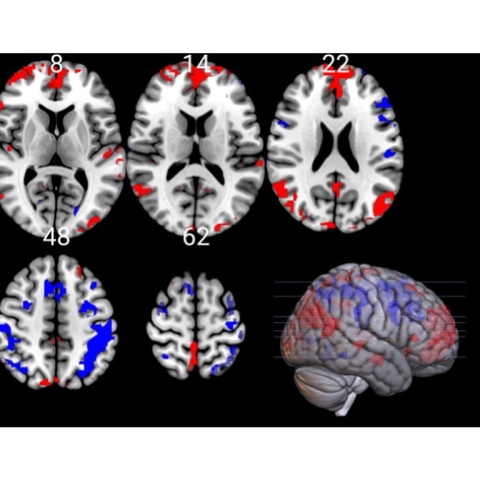

It suggests that cognitive performance is not solely dependent upon the Prefrontal Cortex (PFC) area of the brain, despite it playing an integral role in the performance of tasks.

“But our findings suggest the mechanisms behind CP may not be isolated to this area, and instead we should consider it being the product of a series of coordinated processes widely distributed across different cortical and subcortical regions.”